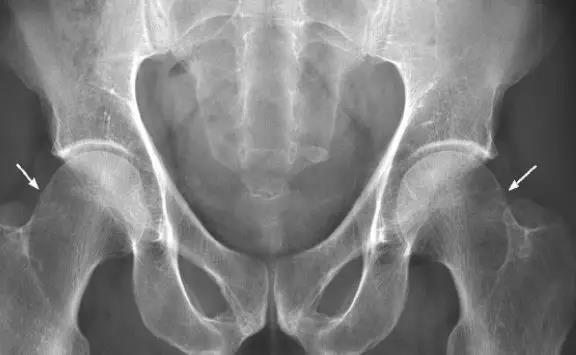

凸轮撞击型FAI▼

- 股骨头颈间的凹陷不足,伴局部的骨质增生。

- 股骨头颈的“ 枪柄样” 畸形。

2、钳夹撞击型

直接表现:髋臼发育不良(髋臼过深、髋臼前倾、髋臼后倾、髋臼后壁过度覆盖)

- 髋关节水平轴位上股骨头颈连接部可见局限性的。线形切迹或凹陷。

- 股骨颈前上区域的囊变及相邻骨皮质增厚。